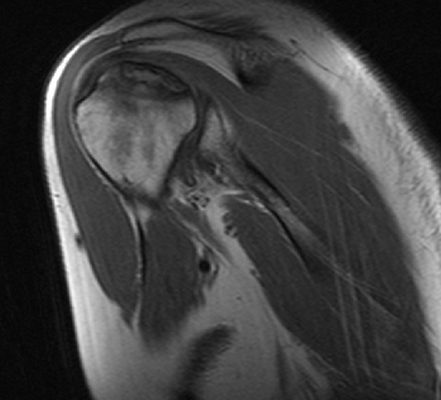

МРТ плечевого сустава, что показывает?

МРТ плечевого сустава

МРТ плеча

Расшифровка фото снимков МРТ плечевого сустава